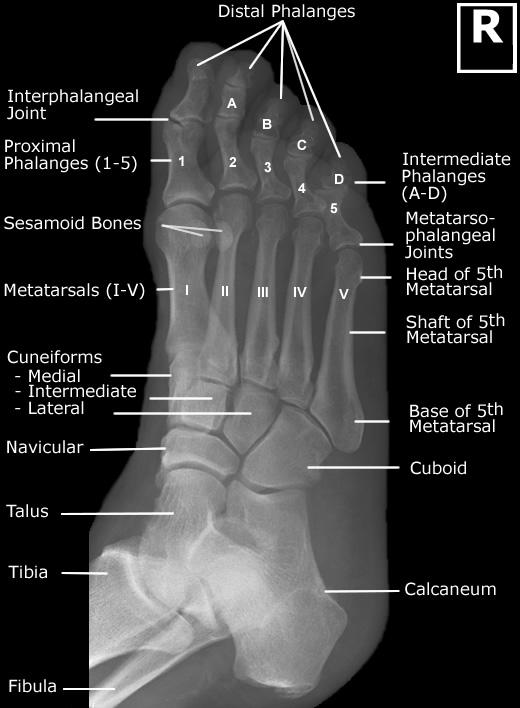

Foot X Ray Anatomy Anatomy Reading Source